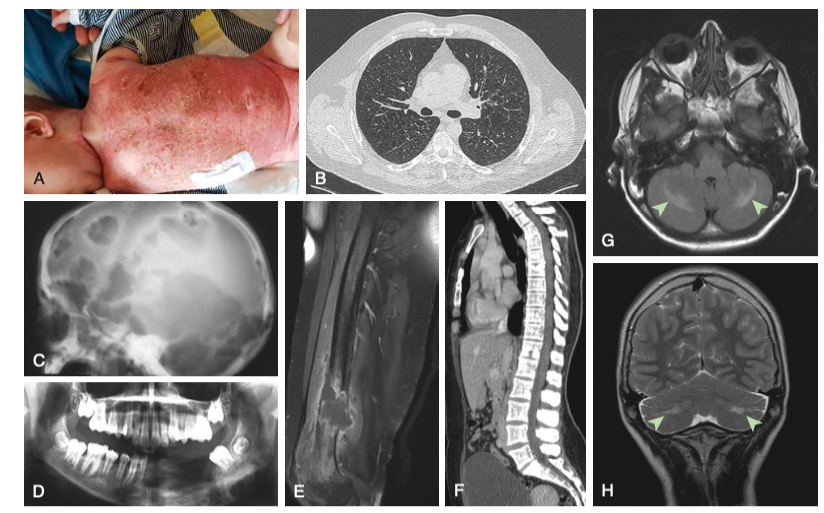

임상양상

단일기관 침범(Single-system LCH)

뼈: 가장 흔함(80%). 두개골, 장골 등에서 통증, 부종, 병적 골절을 유발하는 용해성 병변.

피부: 지루성 피부염과 유사한 발진, 구진, 궤양 등이 기저귀 부위, 두피, 외이도에 호발함.

폐, 간비장비대, 조혈계 감소, 안구돌출, 뇌하수체 침윤 (호르몬 이상) 등

기타: 폐(낭종 형성), 내분비계(요붕증이 가장 흔함), 중추신경계(신경퇴행성 변화) 침범 가능.

진단

뼈 엑스선사진: punched out defect, 지도모양의 병소, 편평 척추, 장골 골절 등